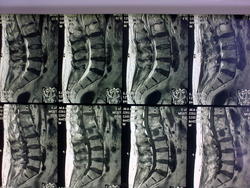

Тела позвонков Д12-L1 разрушены в различной степени, сближены между собой и образуют костный блок неоднородной структуры. Это последствия перенесенного туб. спондилита. В теле L2 определяется костная каверна, вероятно заполненная казеозом, которая переходит через частично разрушенный межпозвонковый диск. Насколько свежи эти изменения сказать трудно без предыдущих исследований. Осталось непонятным, что с позвонками Д6 и Д9. Для туберкулёза такая множественная локализация не характерна. Если больной не имеет архива исследований позвоночника, исключить рецидив туб спондилита не получится.

Не уверена, что при туберкулезе позвонка будет наблюдаться вздутие контура L2, больше склоняюсь к паразитарному поражению. Если пришлют МСКТ потом представлю. Из описания: в теле Л2 определяется жидкостное включение, с перифокальным склерозом, которое распространяется через краниальную замыкательную пластину Л2, через выраженно измененный диск до каудальной пластинки Л1 без изменения целостности последней. Повышен сигнал от дужек Д12-Л2. Кистовидные включения в большой поясн мышце 0,8*6,1 справа, 0,8*5,1 слева, спереди 1,4*3,4. Опять же множественное поражение не рядом лежащих позвонков в анамнезе, самоизлеченных, туберкулезный спондилит больному не ставили, и соответственно не лечили.

Поражение Д12-L2 вполне укладываются в туб. спондилит. Множественного поражения не рядом лежащих позвонков, как и вздутия L2, к сожалению, не вижу. Кистовидные включения в поясничных мышцах - остатки натёчников. Если туб. спондилит не ставили и не лечили, то по какому поводу была инвалидность?

Если рассмотреть эту кисту в Л2 позвонке, она имеет четкие контуры, нет никакого тающего сахара, краниальная пластинка позвонка не разрушена, а деформирована, как бы приподнята, вздута? Был один случай когда мы взяли на учет больного с диагнозом туберкулезный спондилит (все начиналось с бокового поражения 2-х тел, натечного абсцесса (как мы думали) на бедре), а окзался эхинококкоз. Теперь он везде видится. Первые снимки не сохранила. Могу представить только снимки, сделанные после курса протвотуберкулезной терапии, снимки с отрицательной динамикой. Клиника нарастала, паразитарные абсцессы рецидивировали после множественных операций, появились изменеия в печени. Диагноз эхинококкоза гистологически подтвержден.